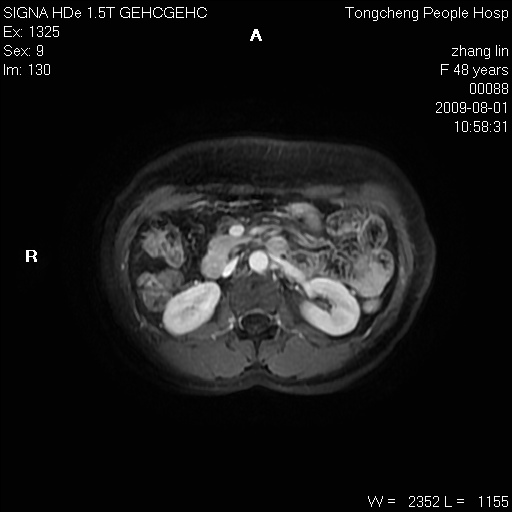

女,48岁。健康体检,彩超发现右肾占位性病变。平素健康。

临床诊断:右肾占位性病变,性质待定(囊肿?肿瘤?)。

上中腹部mr平扫+增强扫描,图像如下:

右肾上极见一类圆形病灶,t1wi呈等信号t2wi呈等高混杂信号,三期增强无强化,边界清---考虑囊肿出血。

同反相位均表现为等信号,病变无强化,考虑含蛋白的囊肿可能,弥散加权相或许有些帮助,